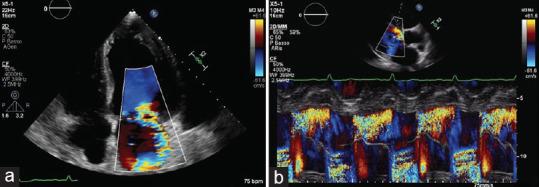

Left ventricular noncompaction (LVNC) is commonly described as a congenital cardiomyopathy characterized by prominent myocardial trabeculae and deep intertrabecular recesses extending in the left ventricular chamber. Clinical presentation can differ considerably from asymptomatic individuals to those presenting with heart failure and other serious complications. Diagnosis is usually made by two-dimensional transthoracic echocardiography or cardiac magnetic resonance. Moreover, even if strain parameters are significantly reduced in patients with LVNC, they are not routinely investigated. Here, we report the case of a previously symptomless patient admitted to the hospital for pulmonary edema. Two-dimensional transthoracic echocardiography showed severe valvular heart disease and left ventricle pronounced trabeculation and remodeling, although speckle tracking echocardiography (STE) demonstrated only mild strain reduction. We, therefore, explore the possibility that STE may be useful to differentiate LVNC cardiomyopathy from LVNC phenotype due to severe remodeling.

左心室心肌致密化不全(LVNC)通常被描述为一种先天性心肌病,其特征是左心室腔内有突出的心肌小梁和深陷的小梁间隐窝。临床表现从无症状个体到出现心力衰竭和其他严重并发症的个体差异很大。诊断通常通过二维经胸超声心动图或心脏磁共振成像进行。此外,即使LVNC患者的应变参数显著降低,也不会对其进行常规研究。在此,我们报告一例既往无症状的患者因肺水肿入院。二维经胸超声心动图显示严重瓣膜性心脏病以及左心室明显的小梁形成和重塑,尽管斑点追踪超声心动图(STE)仅显示轻度应变降低。因此,我们探讨STE是否有助于区分LVNC心肌病与因严重重塑导致的LVNC表型的可能性。